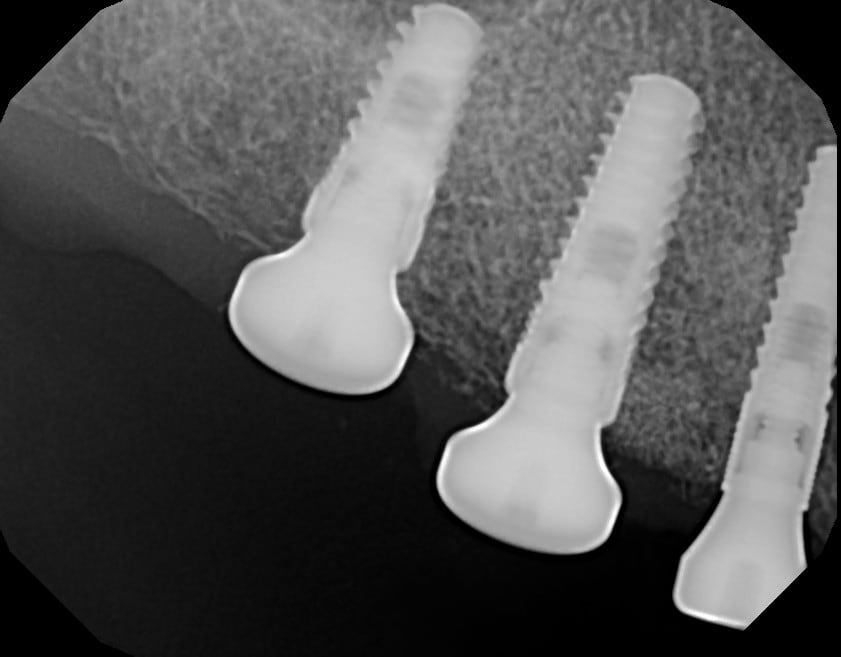

Exo racine région 15

Greffe/expansion zone 14 (que 3 mm d'os au départ)

Pose implants 14-15-16 (il n'y a pas de 7 en bas)

Greffe d'os zone 14-15 (particules, membrane collagène)

Un peu de mucco entre 14-13 (conjonctif)

2e temps 5 mois après pose

Empreinte 1 mois après

Pose couronnes zircone/céram transvissées

Nobel ASC : Angle Screw Chanel pour la 14, car axe pas top

Fermeture puits téflon-compo

Radio